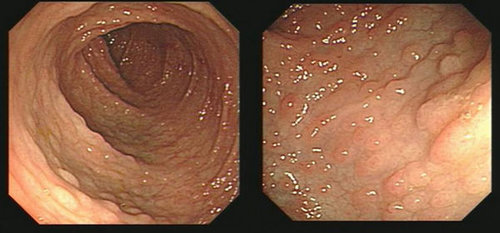

Peutz-Jeghers综合征

Peutz-Jeghers综合征(Peutz-Jeghers’s syndrome,下简称为PJS)又称家族性黏膜皮肤色素沉着胃肠道息肉病,简称黑斑息肉综合征。

本征有3大特征:①黏膜、皮肤特定部位色素斑;②胃肠道多发性息肉;③遗传性。以往认为本病罕见,近年来临床报道病例较多。本病可发生于任何年龄,多见于儿童和青少年,男女发病率大致相同。

Peutz-Jeghers综合征是少见的常染色体显性遗传性疾病,STK11是PJS的易感基因。

PJS主要表现为胃肠道多发性息肉,可见于从胃到直肠的任何部位,尤其好发于小肠,同时有皮肤、粘膜色素沉着,体检时可见到特征性的皮肤或粘膜黑斑,常分布于唇部、口腔粘膜、手指或脚趾、手掌或足底。

内镜下可见散在、多发息肉,常较大并分叶,多有蒂。病理为错构瘤性息肉,其中有平滑肌成分从粘膜肌层如树枝状分枝长入息肉内。

发生胃肠道及卵巢、乳腺、胰腺等部位恶性肿瘤的危险增大,除进行内镜随诊外,尚需注意相应的其他检查。